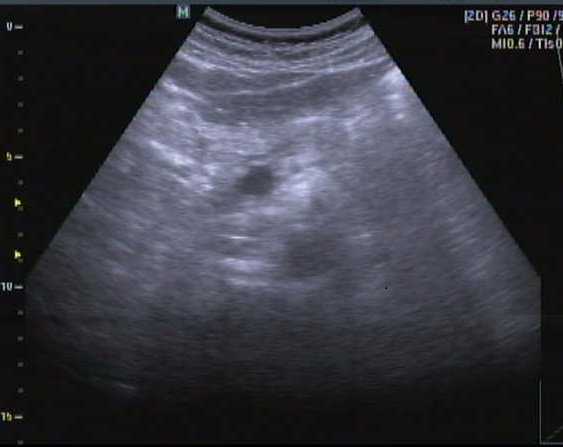

Image echographique

normale du pancreas

:

Normalement echogene du pancreas est

egale ou un peu de superieure echogene du foie , sa

echogen varie avec degree de l'infiltration graisseuse

et encroit avec age . Les bords du pancreas sont regulie , lisse et bien differencie sur

plan ajacents . Sur le coupe transverse , il ressemble un

crochet avec la tete , le corps et le queue . Le canal

de Wirsung normalement < 3mm peut en voyant sur deux tier

des patients et sur echographie il est aechogene ,. Au

niveau de l'ishme ses paroi apparaitre en fine line comme un

rail , au

niveau de la tete il est resemble comme une section

tranverse circulaire . La taille du canal Wirsung peut

augement avec age de 3mm il peut atteidre 6mm . :Le canal

Sntorini et ses canaux secondaire ne peut etre visible a

etat normale .

Sur le coupe sagital de la

ligne median de l'abdomen a travers le foie gauche ,

le pancreas se situe a inferieure du foie gauche , avant le

tronc coeliaque , sa echogen est legerement a

superieure celle du foie |

Image du panreas en coupe transversale .

Sa taille est variable mais normalement : la

tete 25-30mm, l'ishme 20-25mm et le queue

20 -25mm , sa echogene est homogene identique ou

un peu superieure que le foie |